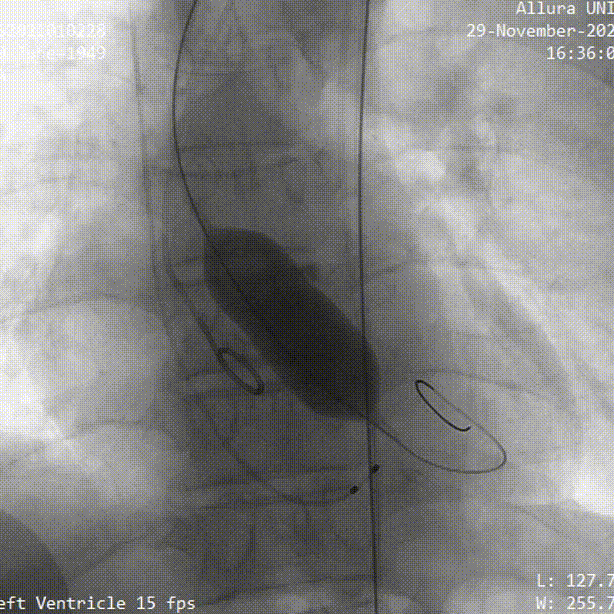

手术过程概览:

主动脉根部造影

23mm球囊预扩

瓣膜定位

瓣膜释放

球囊后扩

术后造影

术后即刻评估

术后压差从104mmHg降至10mmHg,无瓣周漏,瓣膜正常工作,血流动力学即刻得到改善。术后第13小时,患者下床活动。